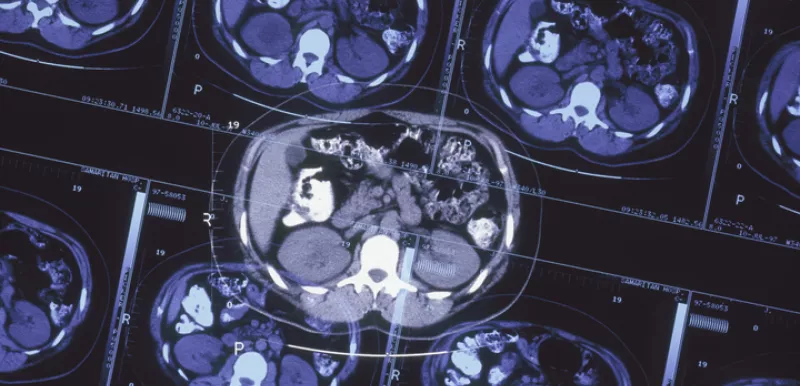

Enzalutamide may not affect seizure incidence among men with prostate cancer, seizure risk factors

Enzalutamide may not increase the incidence of seizure among patients with metastatic castration-resistant prostate cancer (mCRPC) and seizure risk factors, according to a study published in JAMA Oncology.